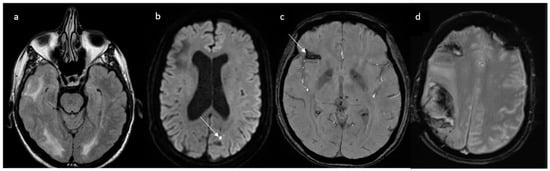

As previously said, vasospasm initially involves only small distal cerebral vessels not depicted by MRA and then centripetally spreads to larger vessels over days or weeks. As a consequence, initial brain MRI is normal in 30–55% of cases, while initial MRA is normal in 22% of cases [9]. Nevertheless, vascular FLAIR hyperintensities as early signs can be visible on T2/FLAIR sequences, even before vasospasm becomes visible on MRA [72]. Well-circumscribed dot or tubular-like appearances of hyperintense lesions running through the sulci, correlating with slow flow on the cortical surface, have been described. These hyperintense vessels (HVs) are often bilateral, involving the territories of the middle cerebral artery (MCA) and posterior cerebral artery (PCA) (Figure 2).

More frequently, HVs are observed in patients with PRES and ischemic stroke, suggesting that they may not only serve as a useful marker of RCVS but may also indicate clinical severity. HVs are distinct from subarachnoid hemorrhage, as they do not appear hypointense on SWI sequences [72]. Vasospasm, on the other hand, can be visualized with magnetic resonance angiography (MRA) or through computed tomography angiography (CTA) (as shown on Figure 3) when it starts involving larger cerebral vessels. As a result, the diagnosis could be challenging in the acute phase and often delayed. In cases of treatment-related RCVS, cerebral edema is more frequently observed and vasoconstriction is more widespread and severe compared to the idiopathic form where vasoconstriction is usually segmental.

Figure 2. Hyperintense vessels on FLAIR images in two patients with RCVS (arrows).